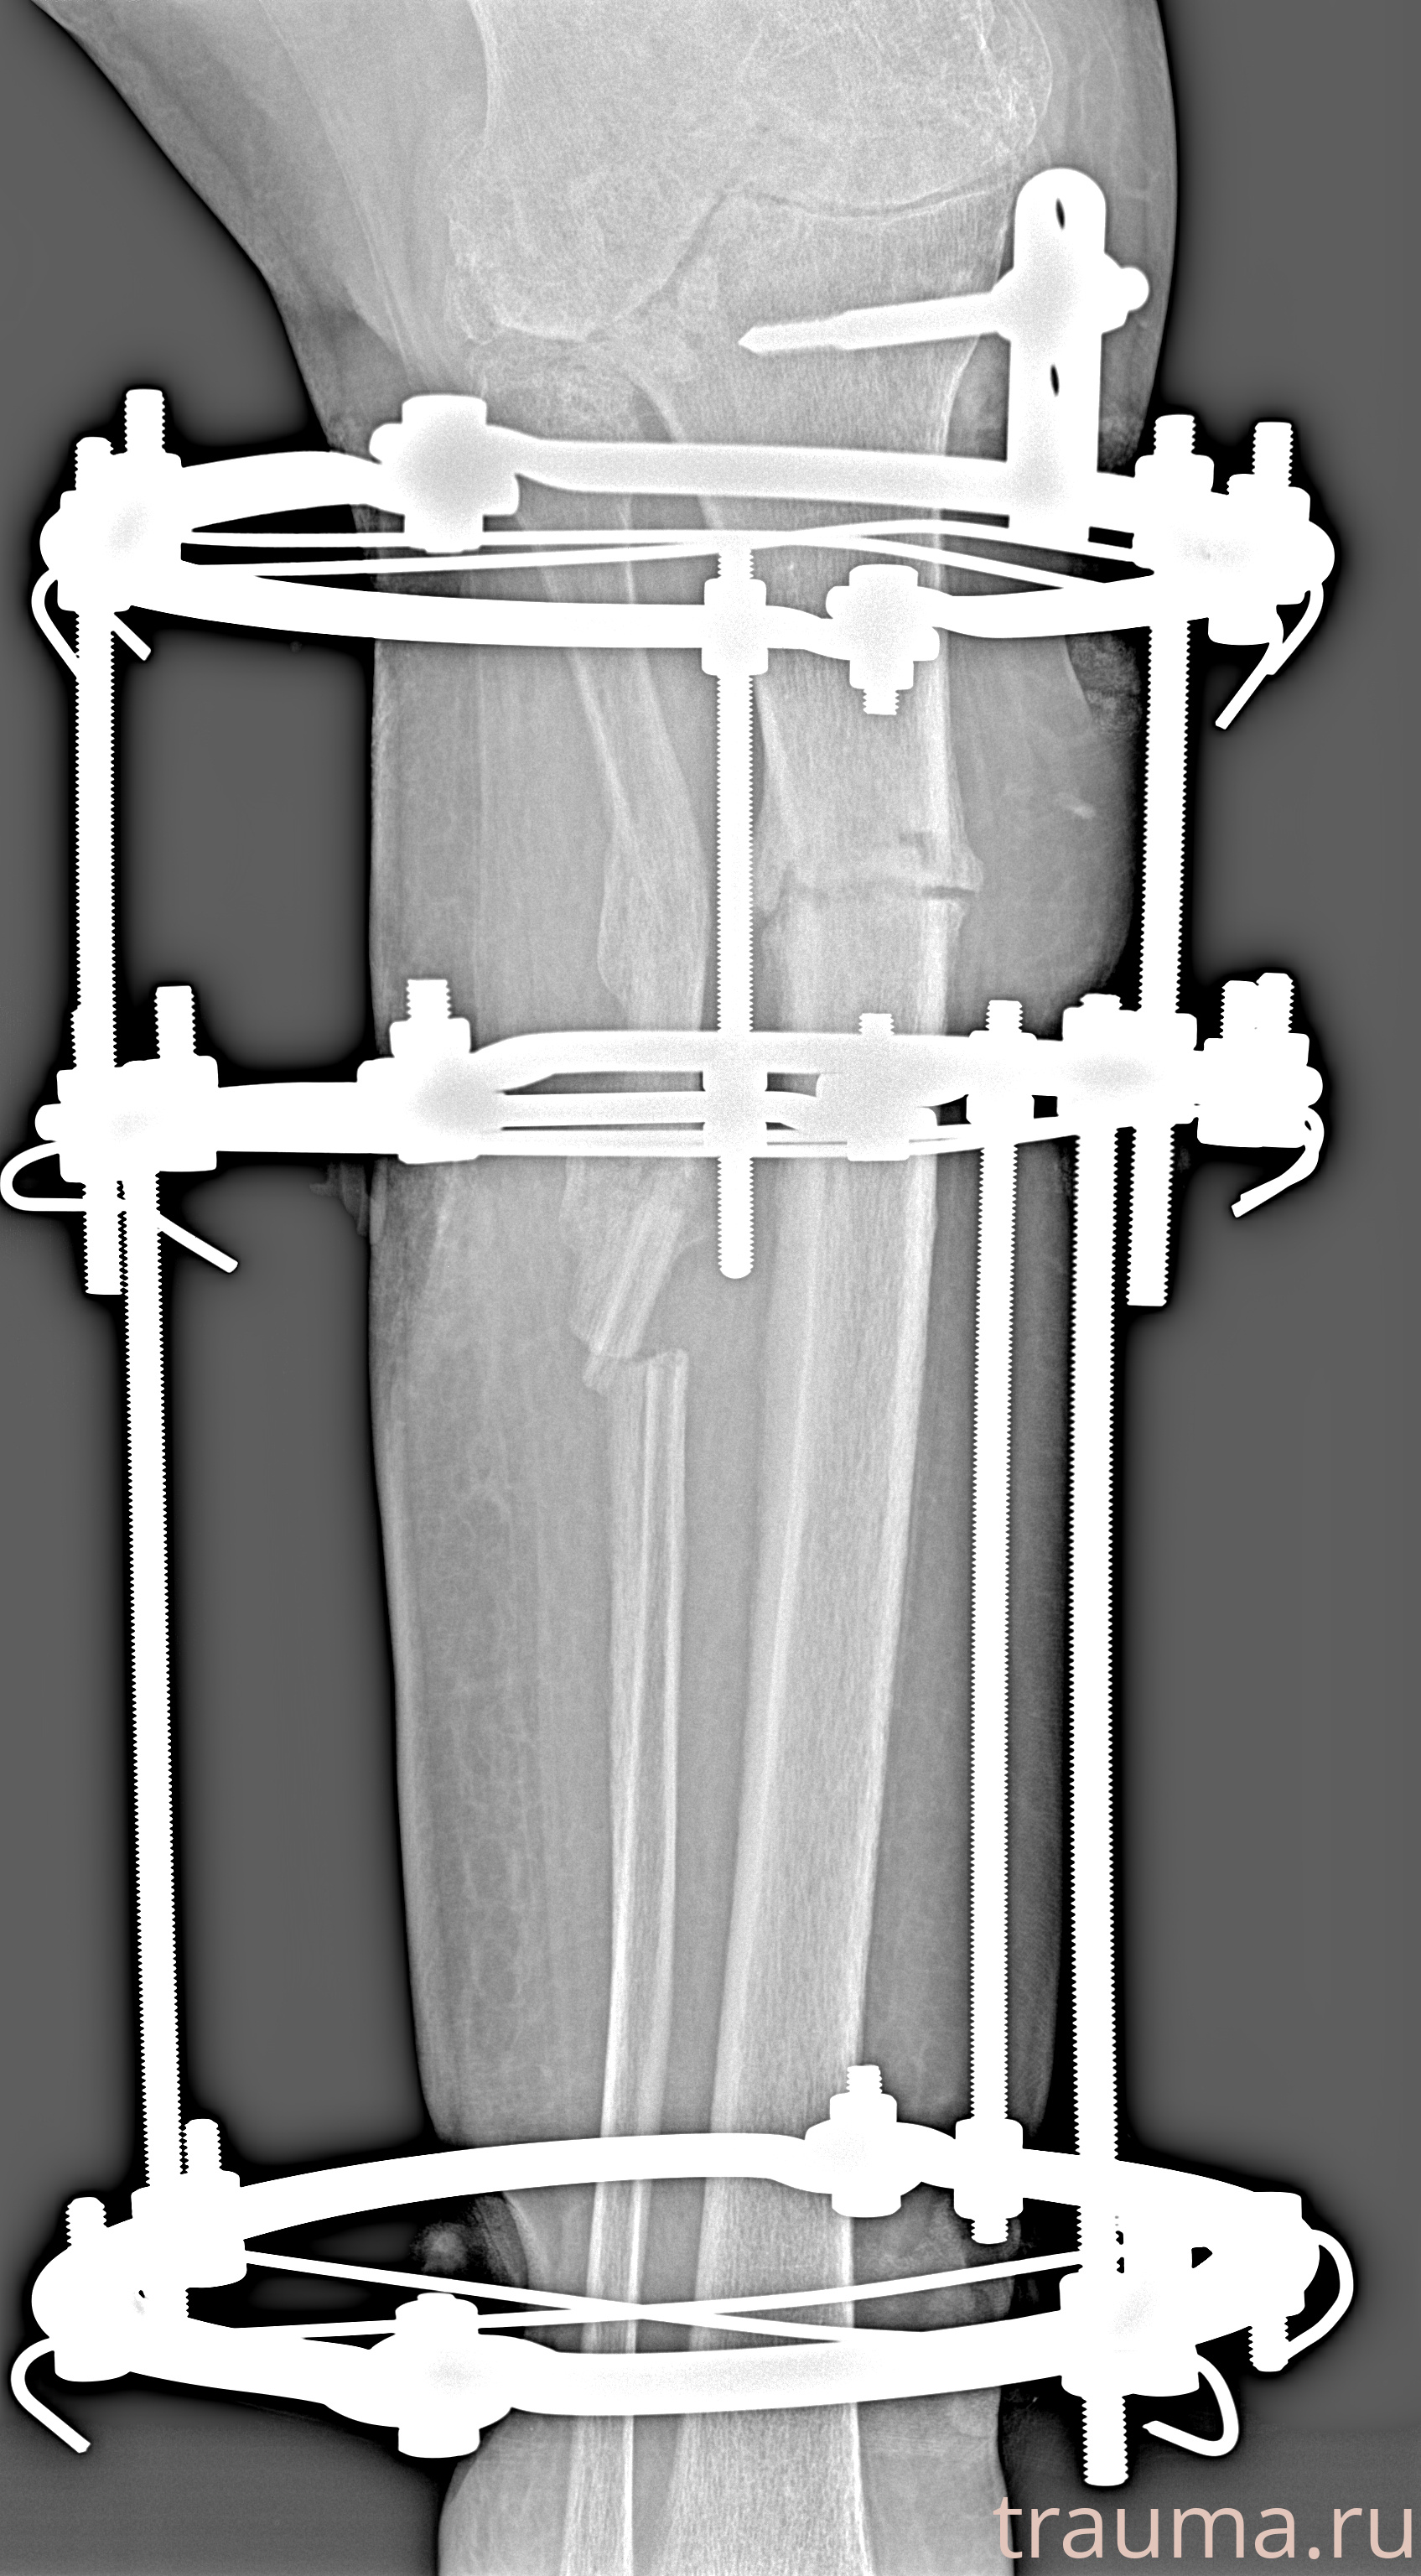

Рентгенограммы

Рентген на дому: по вашему адресу приезжает врач-рентгенолог, травматолог-ортопед с мобильным рентгеновским аппаратом, проводит диагностику травмы или заболевания, делает необходимые рентгенограммы, дает рекомендации по дальнейшему лечению. Получить качественные снимки в домашних условиях возможно благодаря уникальной методике, разработанной МосРентген Центром для института  Склифосовского